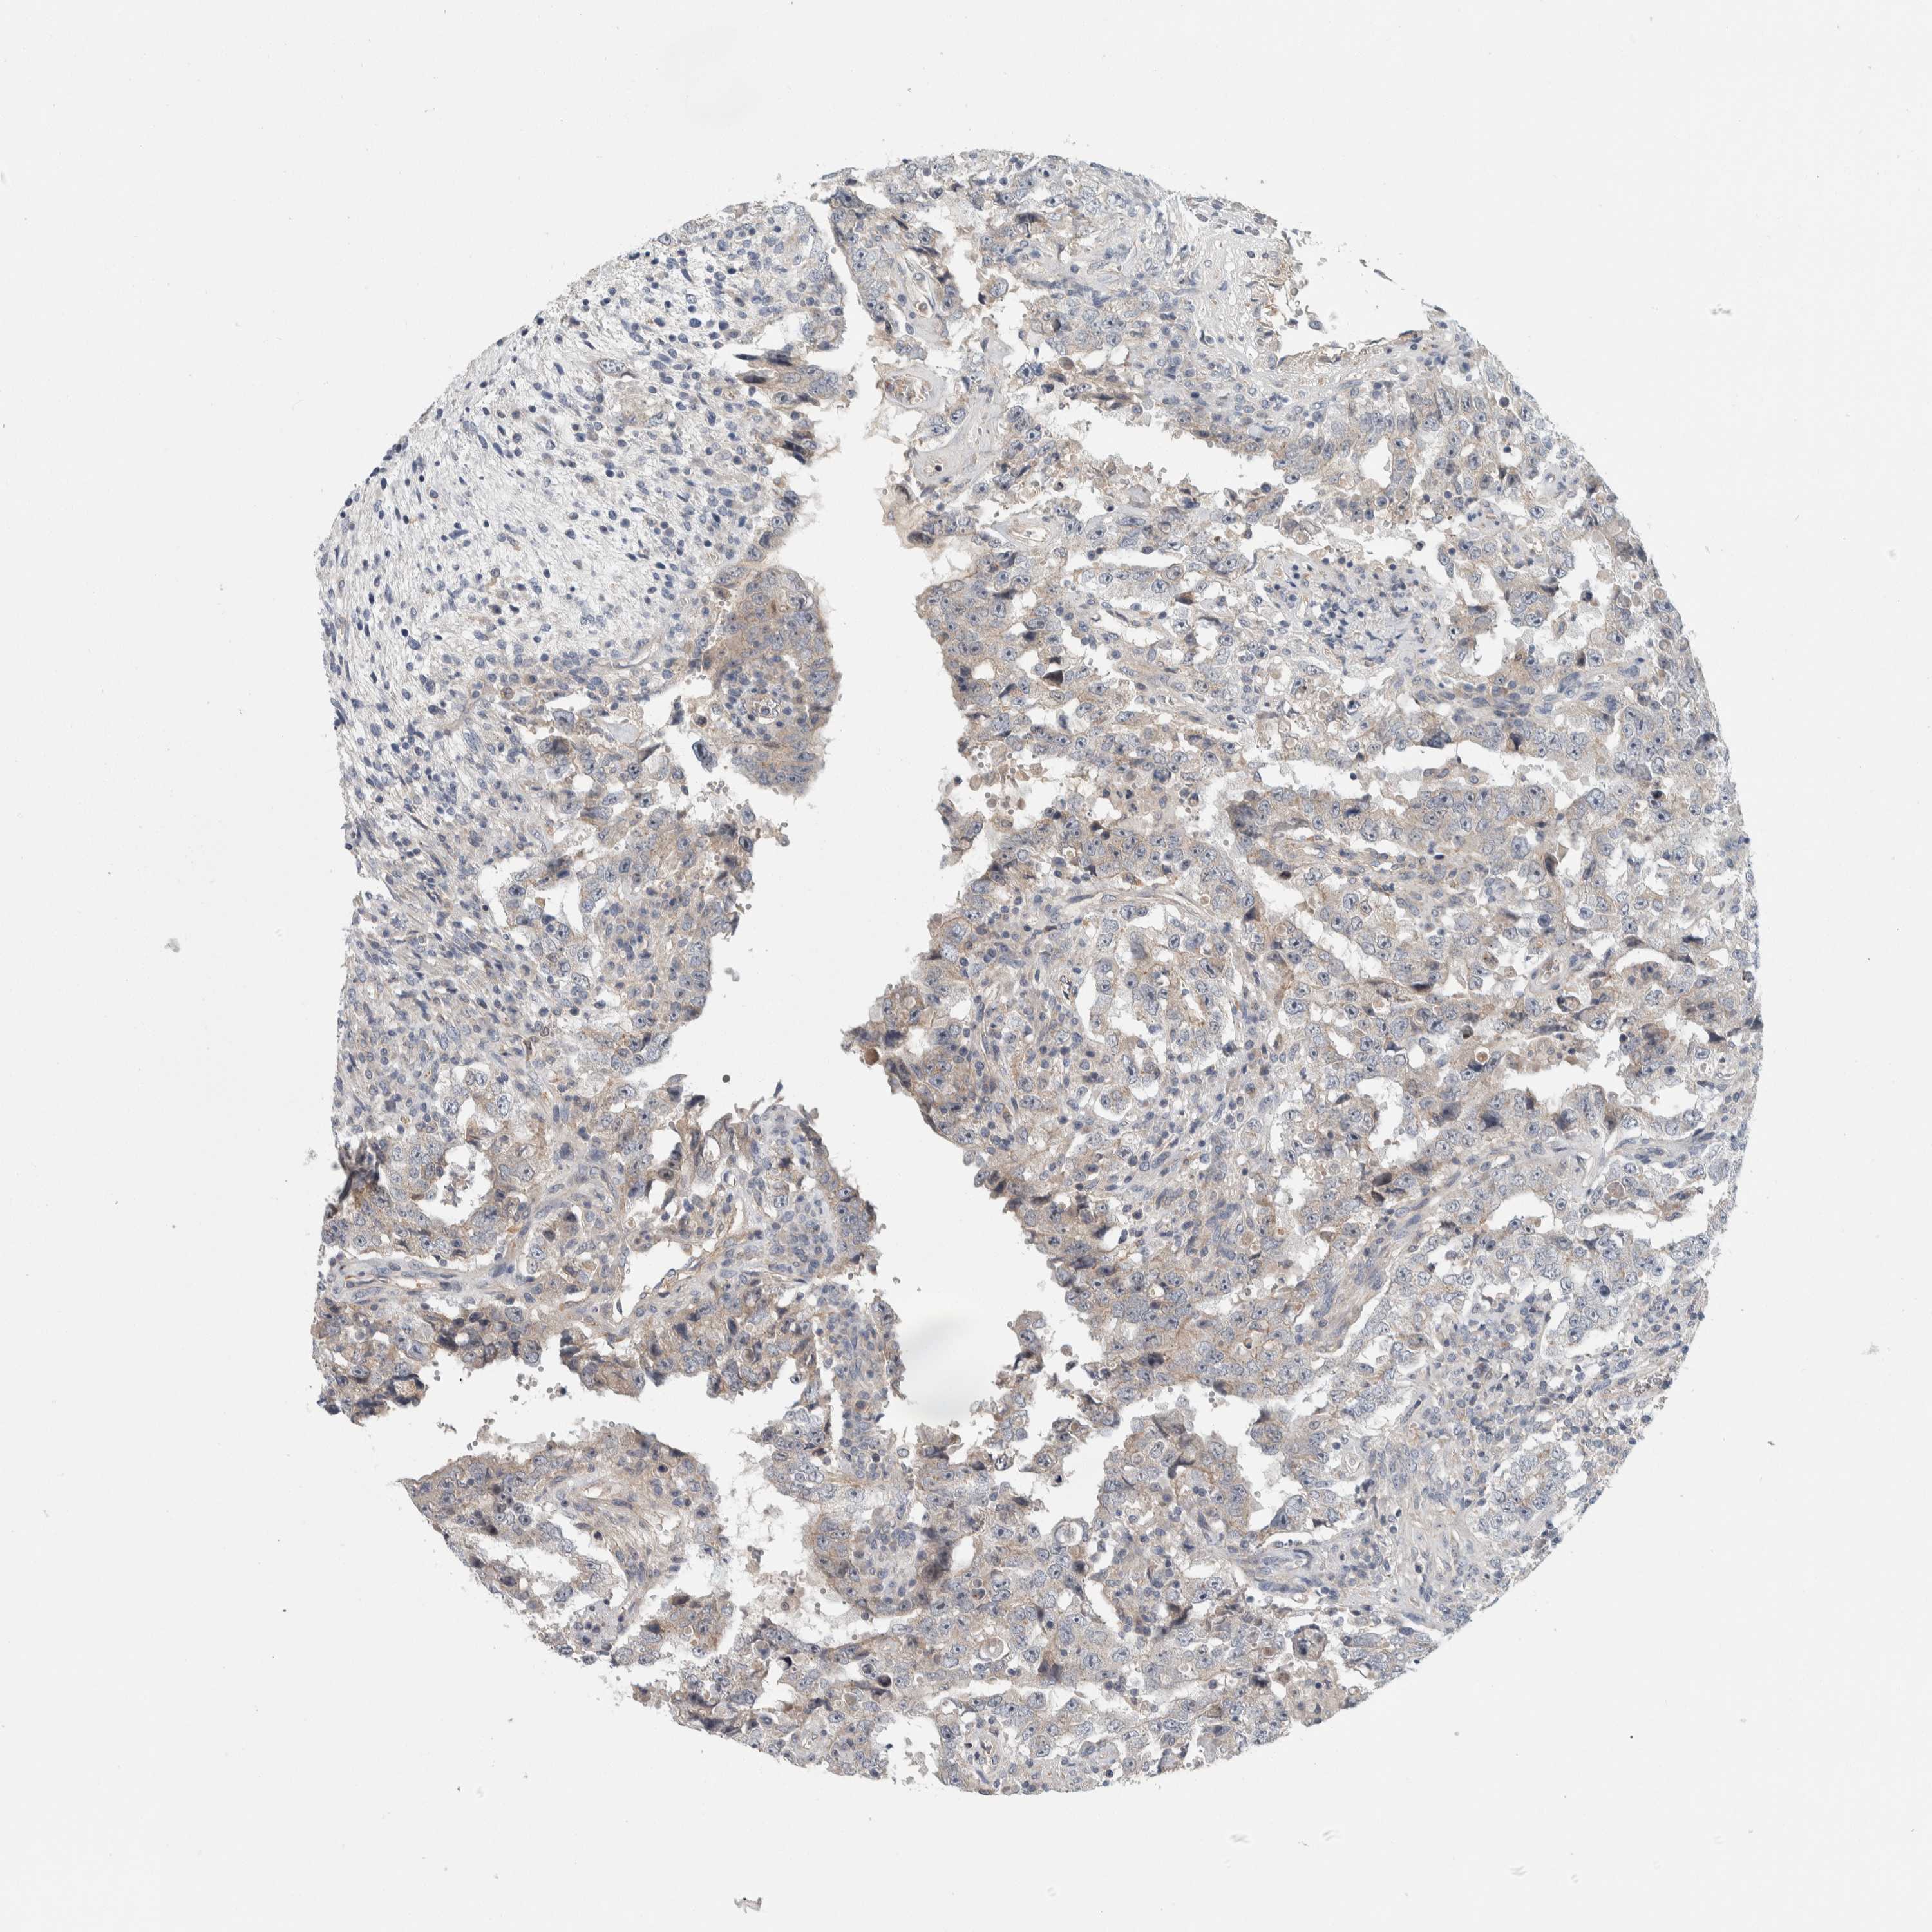

TESTIS CANCER - Protein expressioni

A mouse-over function shows sample information and annotation data. Click on an image to view it in a full screen mode. Samples can be filtered based on level of antibody staining by selecting one or several of the following categories: high, medium, low and not detected. The assay and annotation is described here.

Note that samples used for immunohistochemistry by the Human Protein Atlas do not correspond to samples in the TCGA dataset.

Antibody stainingi

Antibody staining in the annotated cell types in the current human tissue is reported as not detected, low, medium, or high, based on conventional immunohistochemistry profiling in selected tissues. This score is based on the combination of the staining intensity and fraction of stained cells.

Each image is clickable and will lead to virtual microscopy that enables deeper exploration of all samples and also displays staining intensity scores, fraction scores and subcellular localization as well as patient and tissue information for each sample.

Antibody HPA024231

Staining

High

Medium

Low

Not detected

Intensity

Strong

Moderate

Weak

Negative

Quantity

>75%

75%-25%

<25%

None

Location

Nuclear

Cytoplasmic/membranous

Cytoplasmic/membranous,nuclear

Carcinoma, Embryonal, NOS